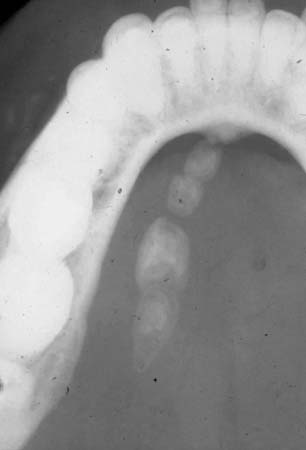

Filme radiográfico oclusal revelando a presença de múltiplos sialolitos no ducto de Wharton esquerdo

Do acervo pessoal do Dr. A. Aguirre; usado com permissão